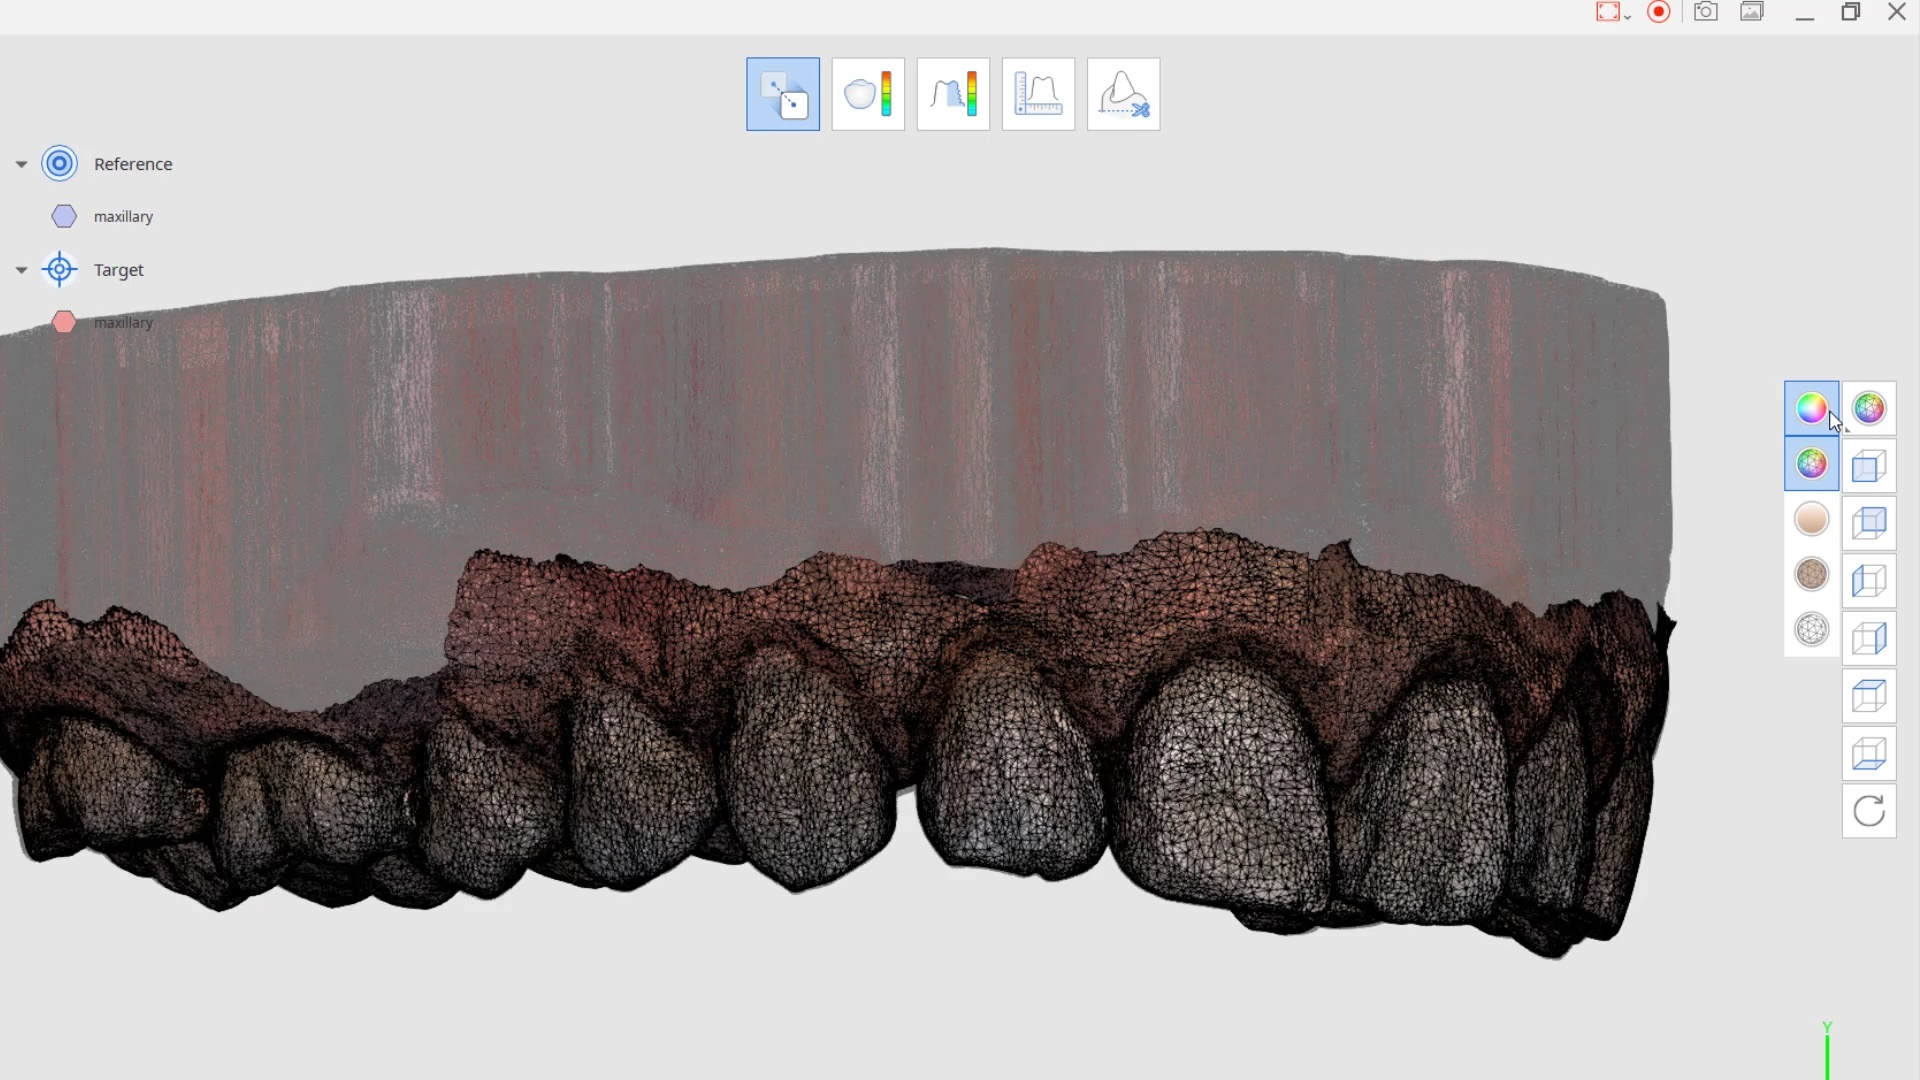

Comparison of Pre-Op Scan and Post Gingivectomy Scan with Medit i500